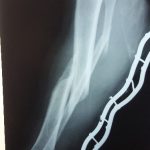

Այս ուսումնասիրությունը հիմնված է 21 հիվանդների (17 տղա, 4 աղջիկ) շարունակական խմբի բուժման արդյունքների վերլուծության վրա, որոնք ենթարկվել են տիտանե էլաստիկ մեխերով վիրահատության։ Հիվանդների տարիքը եղել է 4 տարեկանից մինչև 16 տարեկան։ 9 երեխայի մոտ կոտրվածքի պատճառ է հանդիսացել ձեռքի վրա անկումը, մնացածի մոտ կոտրվածքն առաջացել է վերջույթի ոլորման արդյունքում, վնասվածքի մեխանիզմը եղել է ուղիղ: 19 դեպքերում կոտրվածքները եղել են փակ, իսկ 2 դեպքում՝ բաց։ Ըստ վնասվածքի տեղայնացման՝ դրանք եղել են դիաֆիզար կոտրվածքներ (15 դեպք), պրոքսիմալ մետաֆիզի մակարդակի կոտրվածք (3 դեպք) և հեռավոր մետաֆիզի՝ (3 դեպք): Կոտրվածքային գծի բնույթի համաձայն՝ դիաֆիզային կոտրվածքներից հայտնաբերվել են 6 լայնակի, 4 թեք, 5 պտուտակաձև։ Մի տղայի մոտ (4 տարեկան), որի մոտ առկա էր սրունքի մ/3-ի բաց թեք կոտրվածք տեղաշարժով և մաշկի մինուս հյուսվածքներով, կատարվել է նաև վերքերի առաջնային վիրաբուժական մշակում և կարում՝ ռետինյա արտաթորիչներով։ Սակայն մի քանի շաբաթ անց սկսվել է մաշկի նեկրոզ։ Այդ իսկ կապակցությամբ կատարվել է երկրորդ վիրահատական միջամտությունը։ Կատարվել է մաշկի աուտոտրանսպլանտացիա։ Մաշկի կտորները վերցվել են առողջ ազդրի առաջային մակերեսից: (Նկ 1)

Օգտագործված մեթոդները համահունչ էին հեղինակների նկարագրած վիրաբուժական տեխնիկայի հետ: Հիմնական սկզբունքներն էին՝ ձողերի տրամագիծը, որը համապատասխանում է մեդուլյար լուսանցքի տրամագծի 30-40% -ին, ձողերի թեքությունները նույնական են, բայց հակառակ ուղղորդված և տեղակայված են կոտրվածքի մակարդակում, հարմարեցված վիրաբուժական գործիքների օգտագործումը: